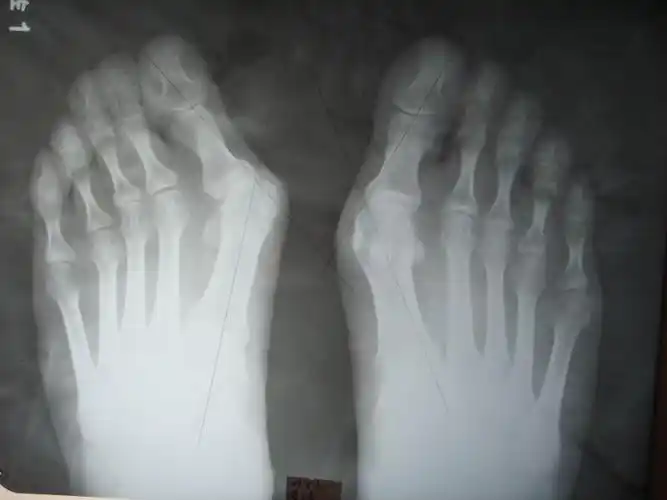

正常足部和大脚骨对比